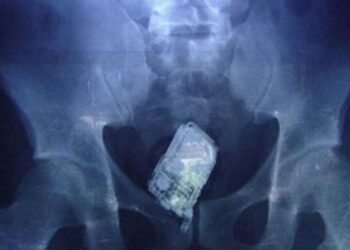

📍 Picassent (Valencia), 17 de abril de 2025 Los teléfonos móviles se han convertido en uno de los objetos más...